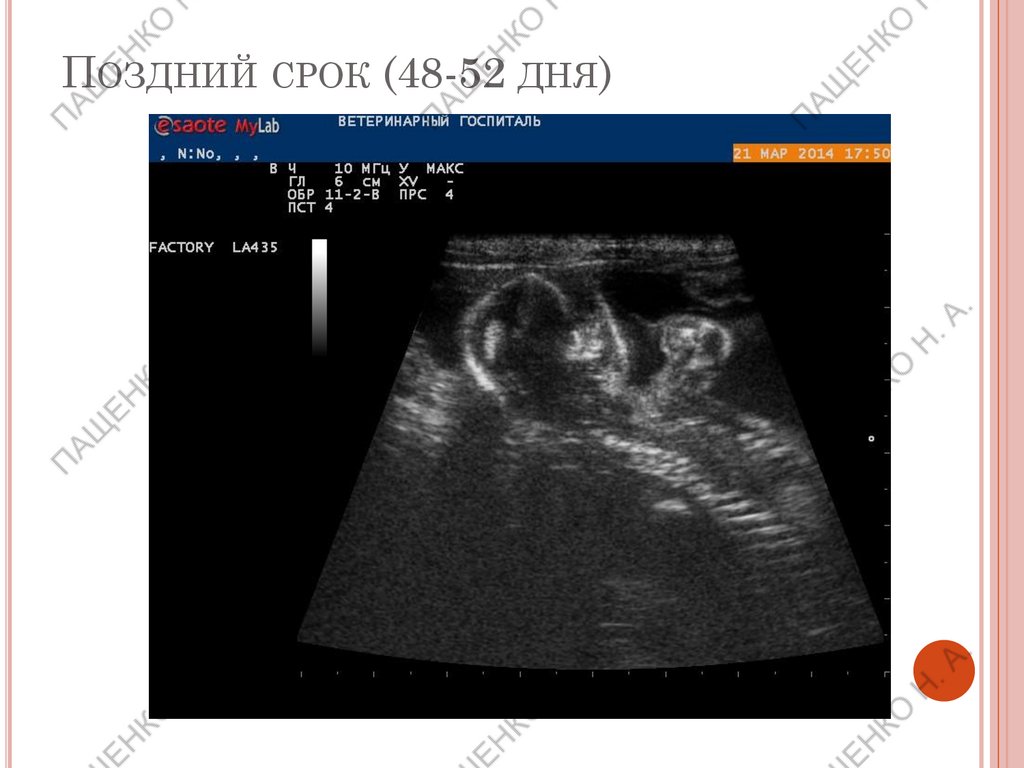

ПОЗДНИЙ СРОК (48-52 ДНЯ)